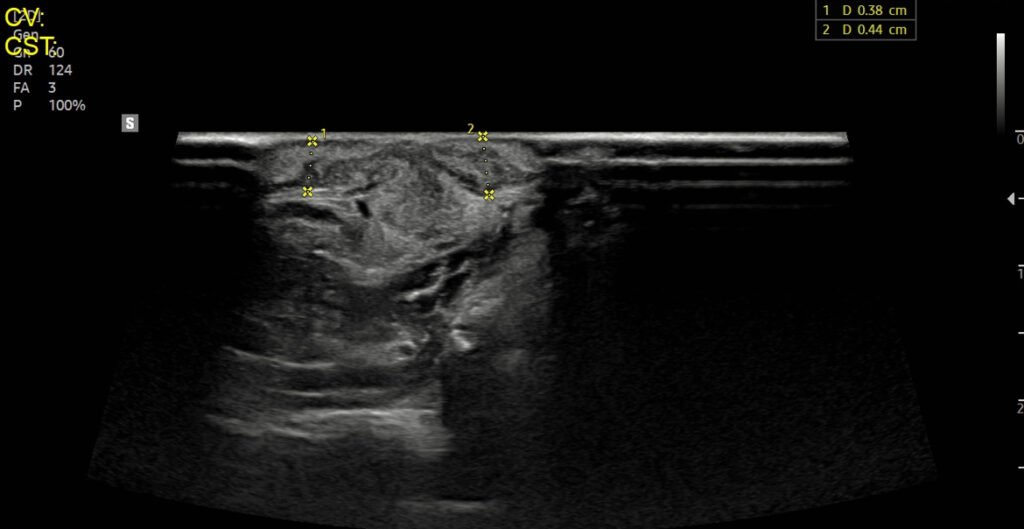

치료 후 재진

치료 경과는 매우 양호했습니다. 치료 후 촉진 시 멍울이 잡히지 않았으며, 촉진 상 통증이 없어졌습니다.   재진 시 초음파 검사에서도 더 이상 fluid(액체) 음영이 관찰되지 않았습니다.